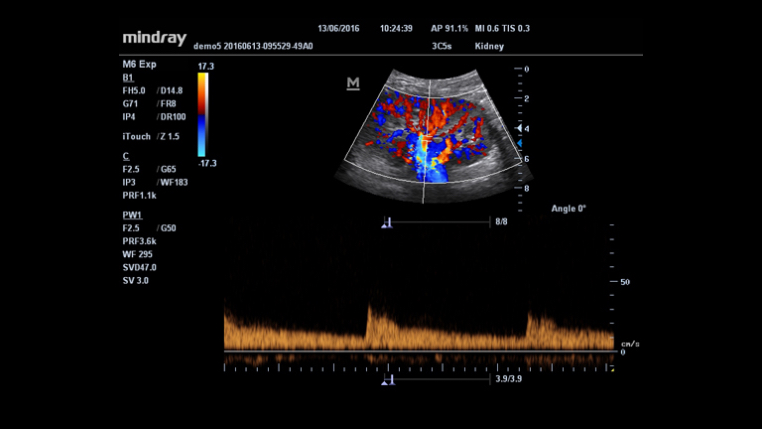

HR Flow?